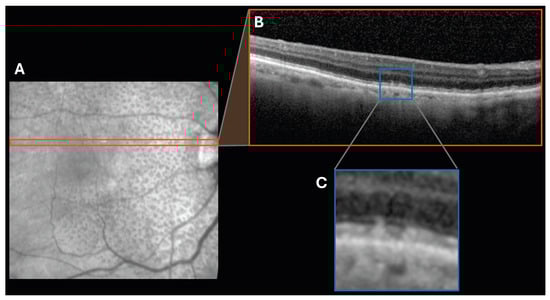

4.4.1. Paracentral Acute Middle Maculopathy Lesions

4.4.2. Retinal Ischemic Perivascular Lesions

| Paracentral Acute Middle Maculopathy Lesions | Retinal abnormalities occurring in the inner nuclear layer of the retina that manifest as hyperreflective bands | Hypertension Carotid artery disease |

| Retinal Ischemic Perivascular Lesions | Focal areas of ischemic thinning occurring along the retinal blood vessels in the inner retina | Hypertension Myocardial infarction/coronary artery disease Cerebral infarction Carotid artery disease Atrial fibrillation |